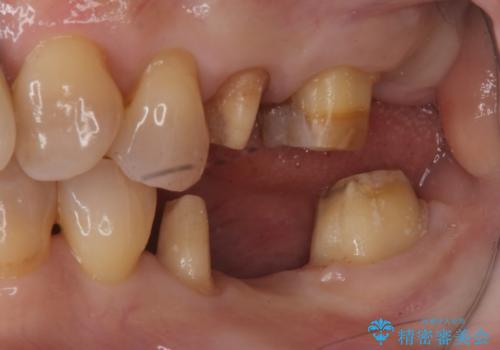

インプラントではなくブリッジにするためには、奥歯の並びを矯正しておいた方がいい状態でした。

抜歯後に部分的にワイヤー矯正を半年ほど行ってから、ブリッジを入れる治療を行いました。